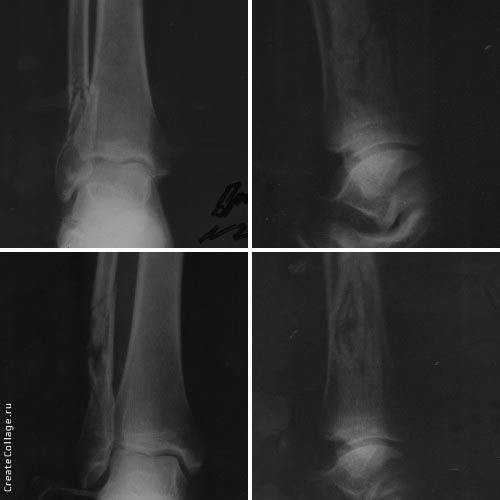

Пациент 36 лет, травму получил 14.03.2017 арматурой за то, что находился

в неположенном месте в неположенное время.

По латеральной поверхности г/ст суставов - ушибленые раны по 3 см. При

поступлении выполнена ПХО ран, наложены гипсовые повязки.

На данный момент раны зажили, отёчность уменьшилась.

Собственно вопрос, стоит ли оперировать лодыжки?